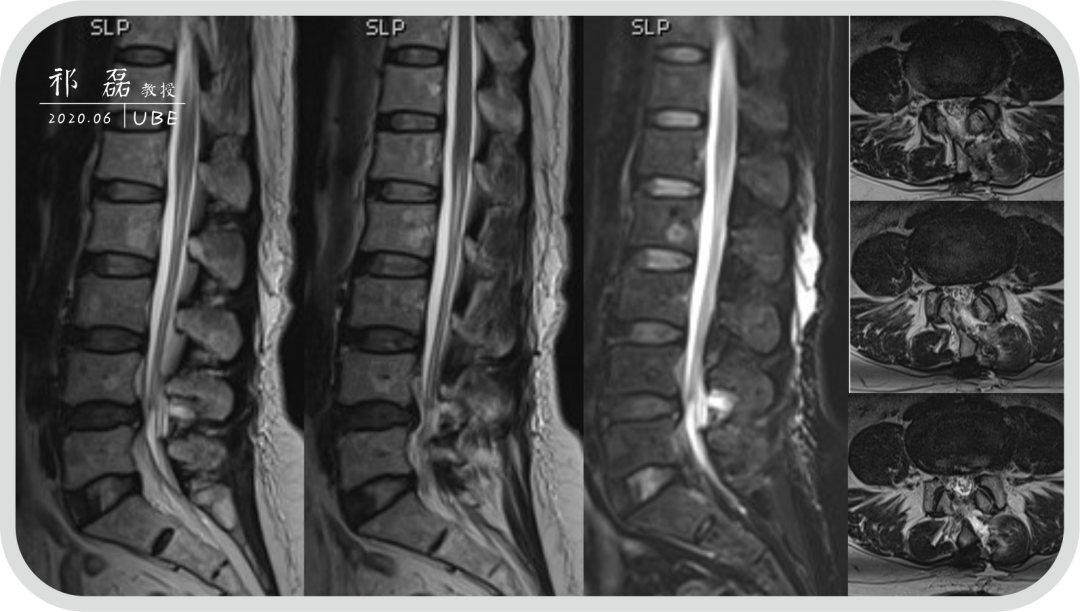

患者:吴某,女,53岁,腰痛及双下肢疼痛麻木5年余,加重1月余,间歇性跛行约200米。于近日入我院查体,下腰椎棘突及椎旁肌深压痛,双下肢感觉运动正常。双侧直腿抬高试验(-),双侧踝反射(-),入院诊断为:腰椎管狭窄症。

图3:腰椎MRI

图8:术后即刻MRI